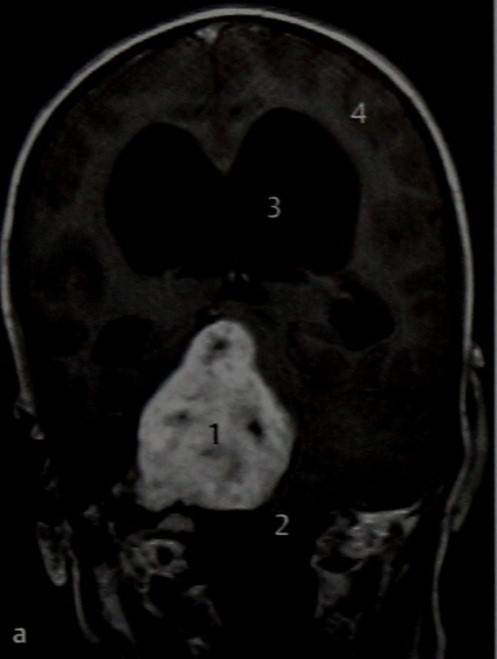

МРТ 9-летнего мальчика, отстающего в умственном развитии, который на протяжении ряда лет не раз был осмотрен ЛОР-специалистами. Тугоухость приписывали наличию ретракционного кармана в барабанной перепонке, пока повышение внутричерепного давления не вызвало неврологический дефицит. а Т1 -взвешенное изображение в вертикальной проекции после введения препарата гадолиния. Шваннома (1) с кистозным компонентом в виде нескольких кисп она растет кверху и значительно сдавливает и оттесняет ствол мозга (2). Расширенные желудочки мозга (3) свидетельствуют о гидроцефалии, связанной с обструкцией ликворных путей, которая вызвала изменение нормального рисунка коры головного мозга (4).